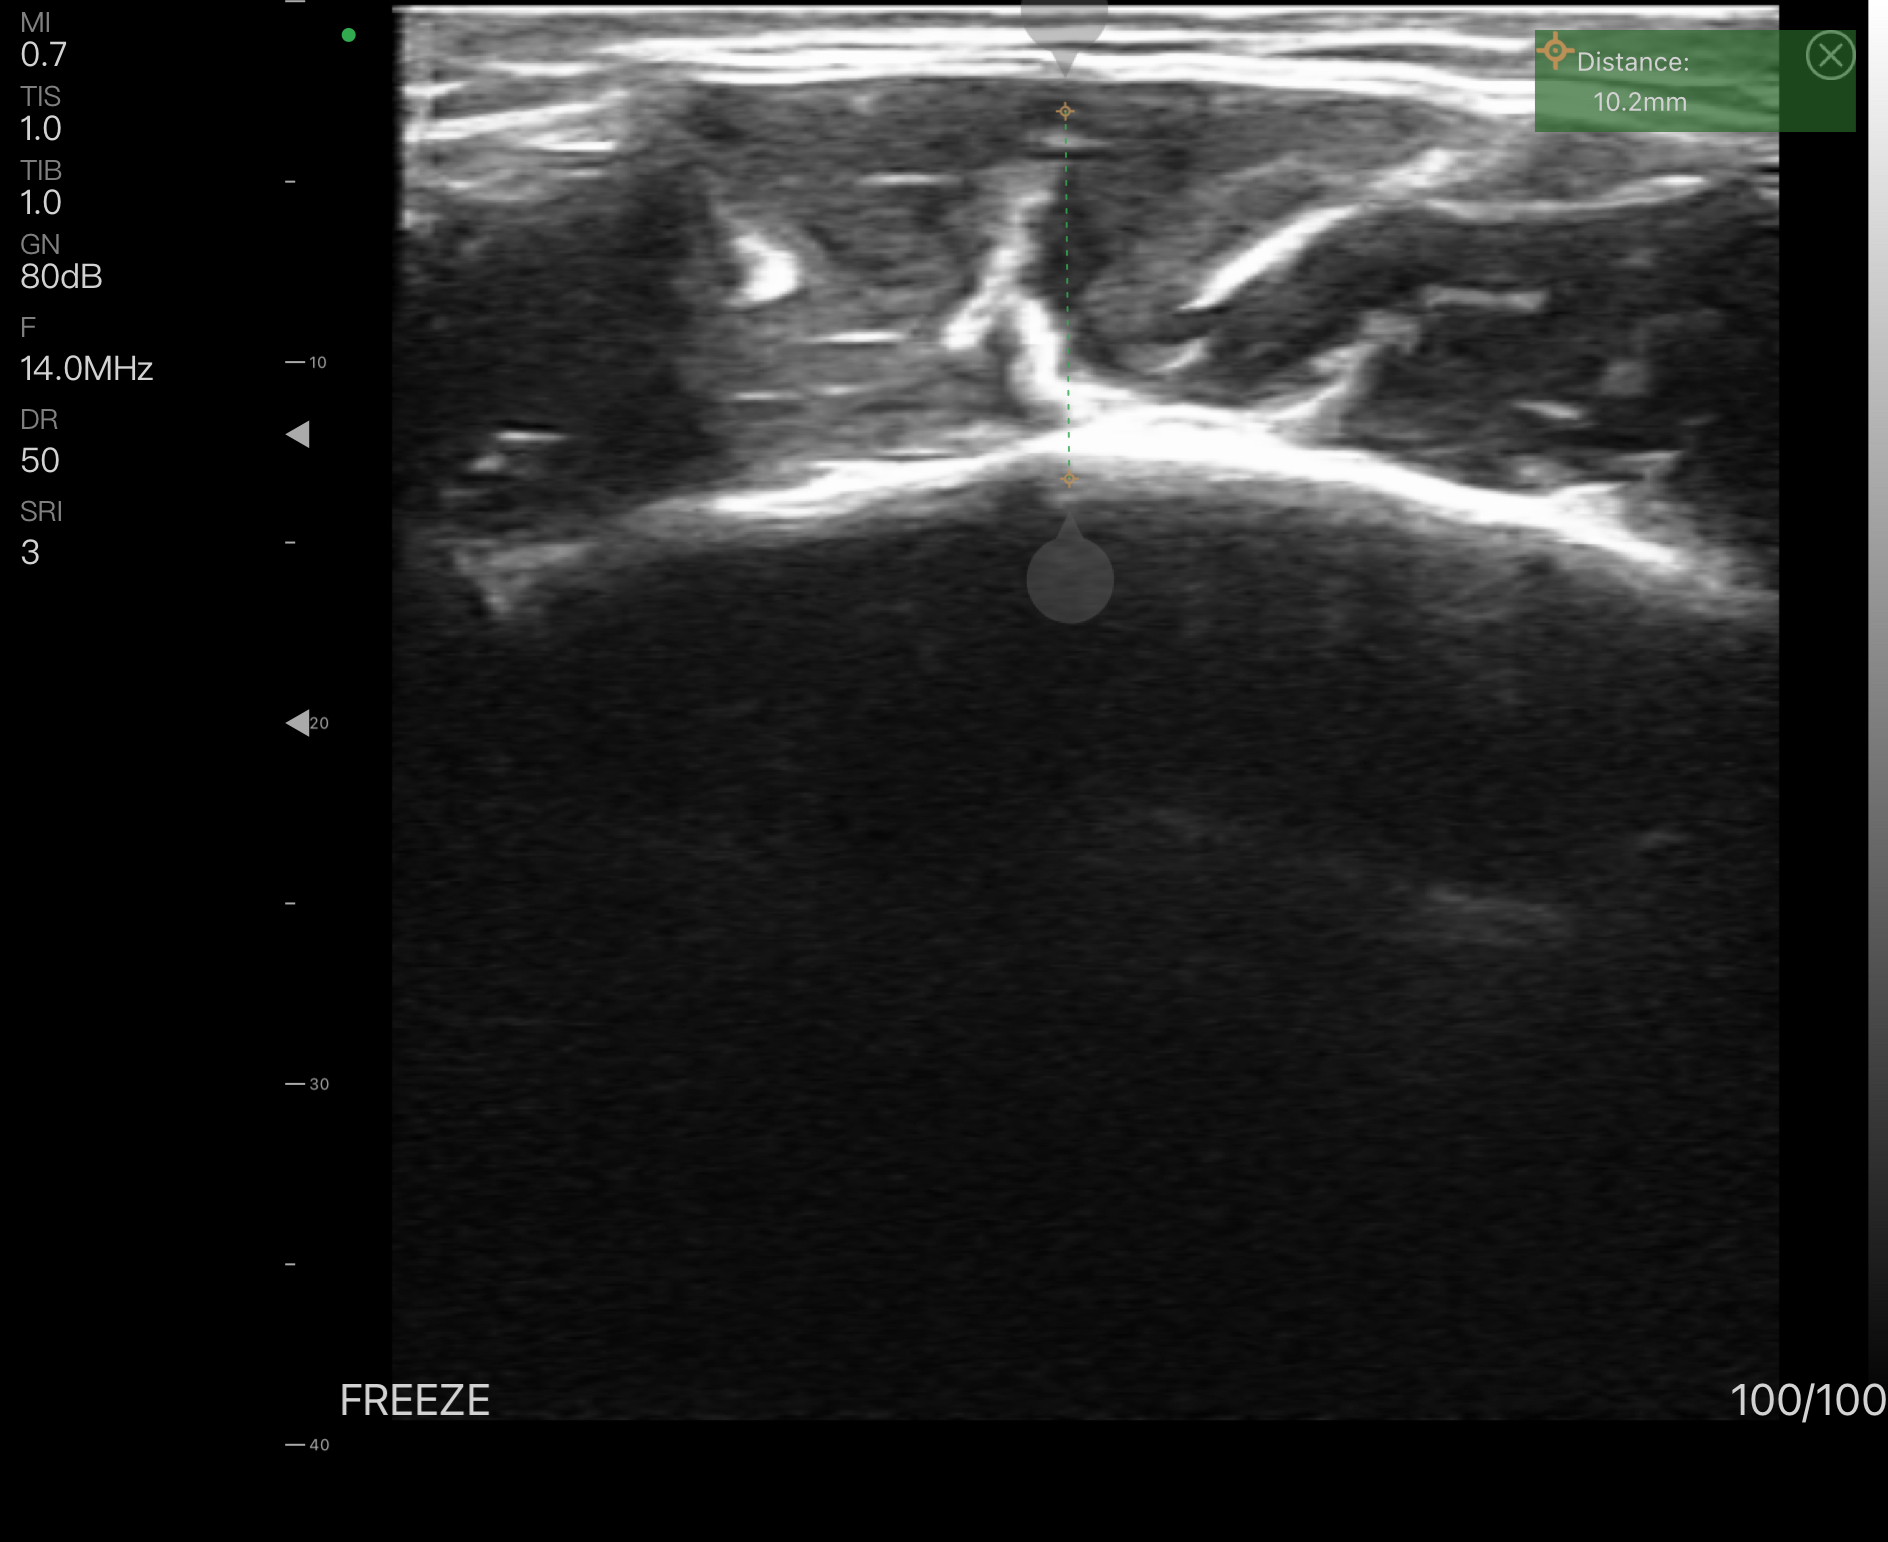

Kasların kalınlıklarını ölçebilmek, invazif işlemlerde büyük avantaj getirir. Enjeksiyon derinliğini hesaplama, usg eşliğinde yapılan enjeksiyonlar hatasız sonuçlar ortaya çıkarır.